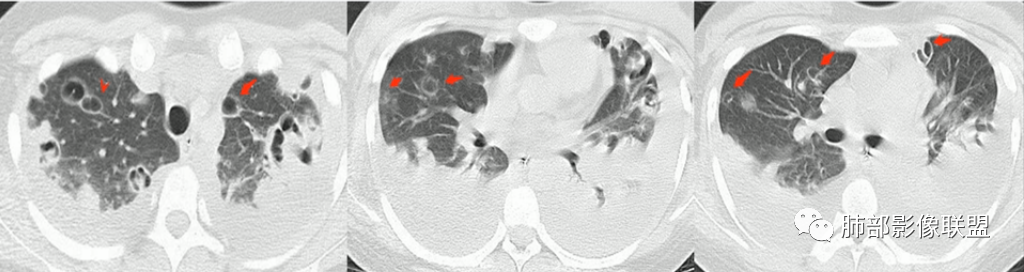

4.容易在短期内出现散在的肺气囊或多发的脓肿病灶;

5.病灶易变,短期内复查CT可见病灶的形态、部位、大小发生变化。

1.外围分布,胸膜下为主,两肺弥漫结节或胸膜下楔形影,边界清,周围伴有GGO

4.囊:张力高,壁薄,内外壁光滑,可有间隔

5.边缘收缩明显,结节密实,边缘收缩、凹陷,周围长索条影,提示吸收好转